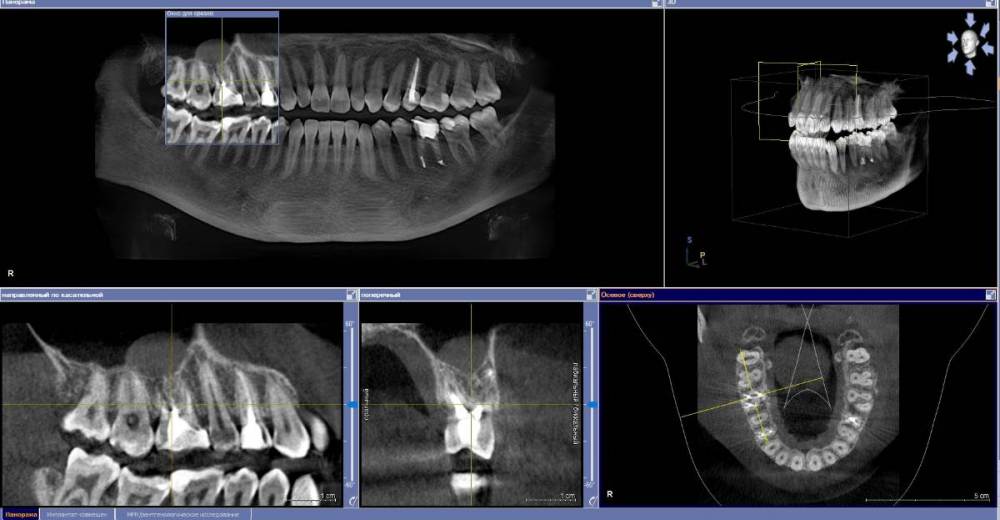

anishuma Опубликовано 1 сентября, 2021 Поделиться Опубликовано 1 сентября, 2021 (изменено) Здравствуйте, прошу помочь разобраться с моими КТ и направить для дальнейших действий. История такая: в 2018 году шестой зуб сверху справа был депульпирован. Долго сохранялись боли при нажатии, при жевании, зуб реагировал на холодной и горячее. Врач, который лечил, заверила что это постпломбировочные боли и скоро пройдет. Коронку побоялась ставить из-за этих болей. Затем примерно через год отлетел кусочек пломбы. Зуб восстановили для дальнейшей установки коронки. На данный момент есть ощутимая реакция на давление, при жевании, при чистки зубной щеткой. Зуб реагирует на холодное-горячее. Один врач сказал, что не видит показаний для перелечивания каналов. Другой врач настаивает на удалении зуба. Подскажите, пожалуйста, где истина, и возможно ли сохранить зуб. Изменено 1 сентября, 2021 пользователем anishuma Ссылка на комментарий

Bier Опубликовано 2 сентября, 2021 Поделиться Опубликовано 2 сентября, 2021 похоже что есть гранулема на корне 2 Ссылка на комментарий

St. Опубликовано 3 сентября, 2021 Поделиться Опубликовано 3 сентября, 2021 +1 к гранулеме. Я бы перелечивала каналы. Но нужно в процессе будет смотреть нет ли трещин в корне. Ссылка на комментарий